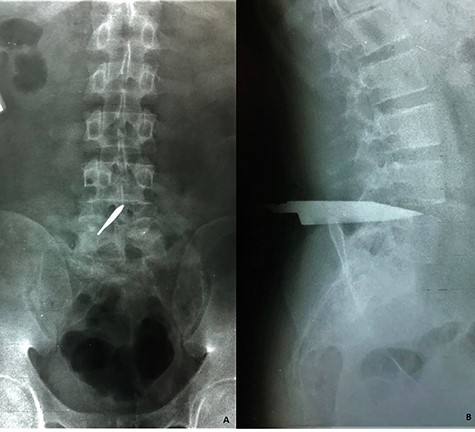

A 21-year-old man arrived at the emergency room with a stab wound in the lumbar spine after alleged subjects attacked him 30 minutes prior to his arrival. Patient was alert and oriented, normotensive, in prone position with a knife projecting through his lumbar spine and a stab wound of ~3 cm (Fig. 1). Physical examination evidenced normal muscular strength, sensitivity, reflexes and pulses; rectal tone was intact. Lumbosacral radiographs were obtained (Fig. 2).

A stab wound of ~3 cm is described, at the lumbar portion of the patient’s spine, with a knife blade projecting from the wound. No active hemorrhage was seen.

Lumbosacral radiographs were obtained revealing a foreign object compatible with a knife blade. (A) Anteroposterior view reveals the object placed within the L4–L5 intervertebral space involving the medullary canal and (B) lateral view shows the object that travels form posterior to anterior up to the L4–L5 intervertebral disc. No evidence of vertebral fractures nor free air were evidenced.